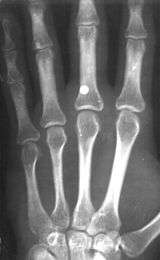

A BB with a velocity of 45 m/s (150 ft/s) has skin piercing capability, and a velocity reaching 60 m/s (200 ft/s) can fracture bone.[4] The potential exists for killing someone; this potential increases with velocity, but also rapidly decreases with distance. The effective penetrating range of a BB gun with a muzzle velocity of 120 to 180 metres per second (390 to 590 ft/s) is approximately 18 metres (60 ft). A person wearing jeans at this distance would not sustain serious injury. However, even at this distance a BB still might penetrate bare skin, and even if not, could leave a severe and painful bruise. The maximum range of a BB gun in the 120 to 180 m/s (390 to 590 ft/s) range is 220 to 330 metres (240 to 360 yd), provided the muzzle is elevated to the optimum angle.

- ↑ C. L. Tsui, K. L. Tsui, Y. H. Tang (2010). Ball bearing (BB) gun injuries